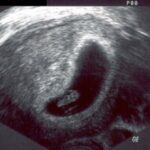

El momento clave para un test de embarazo positivo es aquel en el que se detecta la presencia de la hormona hCG en la orina o en la sangre de una mujer. La hCG, también conocida como la hormona del embarazo, comienza a producirse en el cuerpo de la mujer después de la fecundación del óvulo por el espermatozoide.

Normalmente, los tests de embarazo caseros detectan la presencia de hCG en la orina de la mujer. Estos tests funcionan mediante inmunocromatografía, una técnica que utiliza anticuerpos para detectar la presencia de la hormona. Generalmente, se recomienda realizar el test de embarazo a partir del primer día de retraso menstrual, ya que en ese momento los niveles de hCG suelen ser lo suficientemente altos para ser detectados.

Por otro lado, los tests de embarazo de sangre son realizados en laboratorios y son considerados más precisos que los tests caseros. Estos tests pueden detectar la presencia de hCG en la sangre antes que los tests caseros, incluso antes de la fecha esperada de la menstruación.